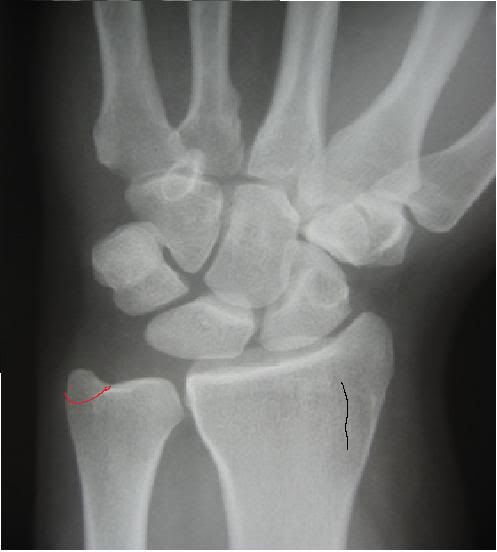

This is what my wrist looks like, taken the little nobbly bit off on the left shown in red, this is the bit that is properly broken. On the right in black, i think there is some kind of fracturing, but does not reach the head or out to the side. nothing is displaced and everything is in good alignment.

This should be a straight forward heal, shouldn't it? Any experiences?

I think you are describing an Ulnar styloid process fracture, which is not considered to need much in the way of treatment as far as I know.